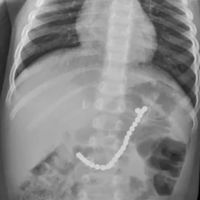

Evita empezar el año con un susto. Así debes darle las uvas a los niños para que no se atraganten

ConsejosLa noche del 31 de diciembre, como es tradición en España y en otros países, celebraremos la Nochevieja y daremos la bienvenida al nuevo año comiendo las 12 uvas. Pero cuando hablamos de niños pequeños, aunque para ellos puede parecer un...